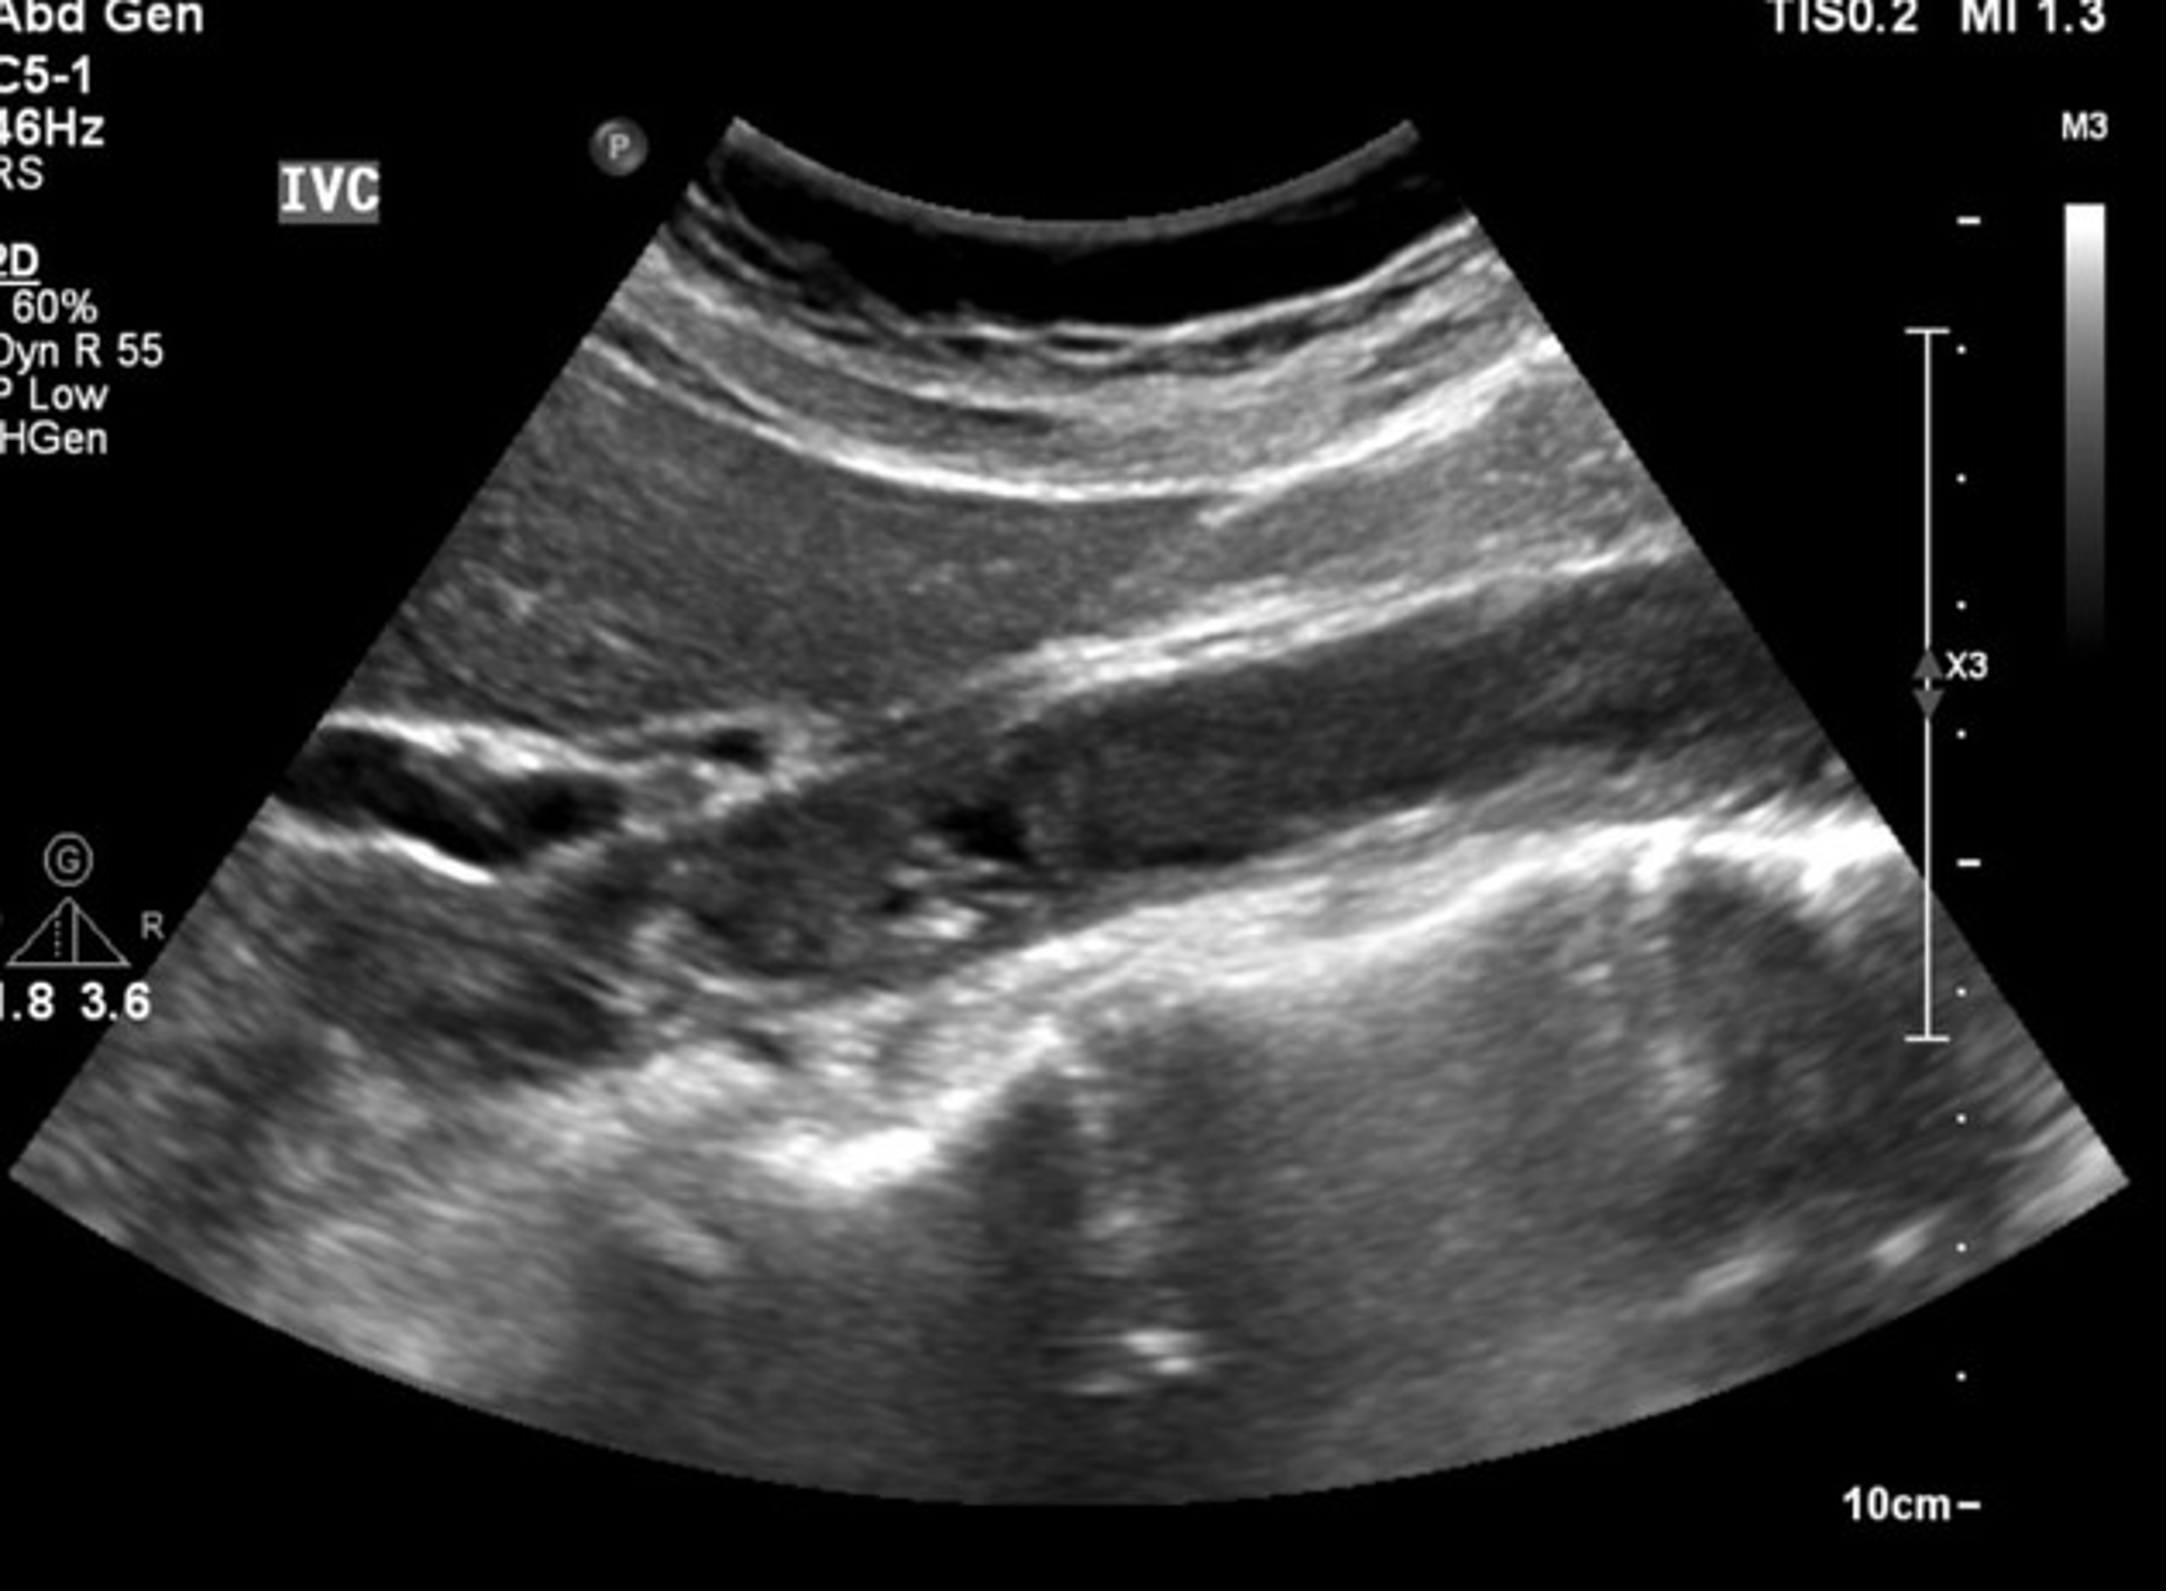

<p>In this sagittal plane, what is this structure?</p>

In this sagittal plane, what is this structure?

<p>What is this image showing?</p>

What is this image showing?

Tumor Invasion of the IVC

<p>What is this image showing ?</p>

What is this image showing ?

Thrombus in the IVC